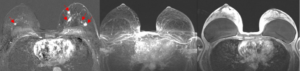

Magnetresonanz-Mammographie

Das bundesweite Mammographie-Screening richtet sich an Frauen zwischen 50 und 70 Jahren und ermöglicht die Entdeckung früher Veränderungen – oft noch bevor Beschwerden auftreten. Ergänzend kommt heute die Tomosynthese zum Einsatz, die durch Schichtaufnahmen die Bildqualität verbessert.

Dennoch reicht die Mammographie allein nicht immer aus. Gerade bei jüngeren Frauen mit dichtem Brustgewebe können kleine oder diffuse Veränderungen schwer erkennbar sein.

Daher bieten wir zusätzlich die MRT-Mammographie als besonders sensibles Verfahren an. Sie kommt ohne Strahlenbelastung und ohne schmerzhafte Kompression aus. Während der etwa 20–25-minütigen Untersuchung in Bauchlage wird nach Gabe eines gut verträglichen Kontrastmittels die Durchblutung der Brust dreidimensional dargestellt. So können auch kleinste oder aggressivere Tumorformen zuverlässig erkannt werden.

Neuere Studien zeigen, dass die Magnetresonanz-Mammographie deutlich mehr tumoröse Veränderungen als die konventionelle Mammographie erfasst und die Prognose der Patientinnen signifikant verbessert(3),(4). Die außerordentlich hohe Empfindlichkeit („Sensitivität“) der Methode führt auch dazu, dass die Wahrscheinlichkeit eines innerhalb des üblichen Zweijahres-Zeitraums zwischen den Screening-Mammografien erstmals nachweisbaren Tumors (sog. „Intervallkarzinome“) gegen Null tendiert(5). Im Umkehrschluss gilt: Zeigt die Magnetresonanz-Mammographie keine Auffälligkeiten, kann weitgehend risikolos auf eine Biopsie verzichtet werden.

Auch bei Frauen, bei denen bereits Brustkrebs festgestellt wurde, hilft die Magnetresonanz-Mammographie weiter, da sie das Ausmaß der Erkrankung genauer erkennen lässt und einen eventuellen Befall auch der anderen Brust zeigt, der in immerhin 3-5% der Fälle vorliegt, so dass dann eine entsprechende Optimierung der Therapie möglich wird(6),(7). Insbesondere Frauen vor den Wechseljahren mit häufig noch dichtem Brustdrüsengewebe profitieren von einer präoperativen Magnetresonanz-Mammographie(8).